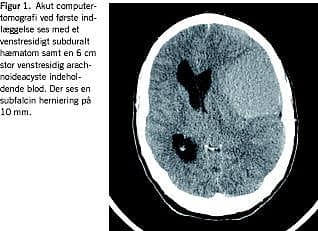

Akut computertomografi viste et venstresidigt subduralt let hyperdenst hæmatom kombineret med en 6 cm stor venstresidig temporofrontal arachnoideacyste, som indeholdt blod. Der var subfalcin herniering på 10 mm (Figur 1 ).